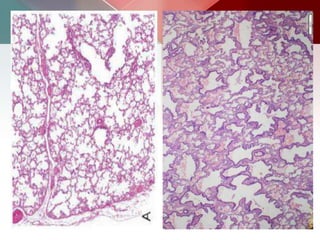

Alveoli which are distended with honey- combed, foamy, brightly eosinophilic material .

There is a scanty inflammatory infiltrate composed

mainly of monocyte, occasional plasma cells and histiocytes.

a) pneumo cystitis carnii pneumonia :

 Cysts vary in size, shape, number, wall thickness

o Thin-walled (<3mm), usually air-filled

o Usually multiple, bilateral

o May be intraparenchymal or subpleural

o upper lobe predominance

 Cystic disease now occurs in 10-34% PCP cases

 Cysts in HIV patient are highly suggestive of PCP

Lung cysts are usually multiple, thin walled and bilateral, but range in size, shape and

distribution